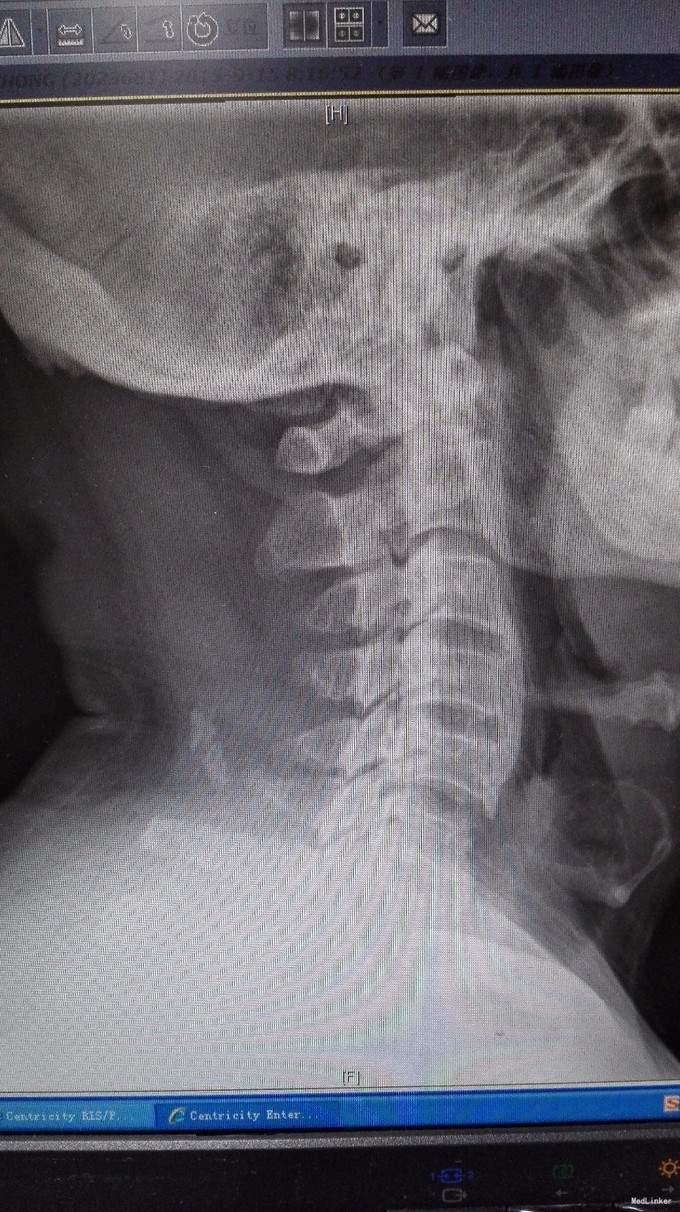

查体:双手麻木感,肱三头肌肌腱反射活跃,左侧髂腰肌4级,臂丛牵拉实验阴性,椎间孔挤压实验阴性。 辅查:CT:C2-7椎间盘突出,继发性椎管狭窄,OPLL,OFL。

诊断:混合型颈椎病(脊髓型+神经根型) 治疗:颈后路3-7单开门椎管扩大成型术(锚定法)